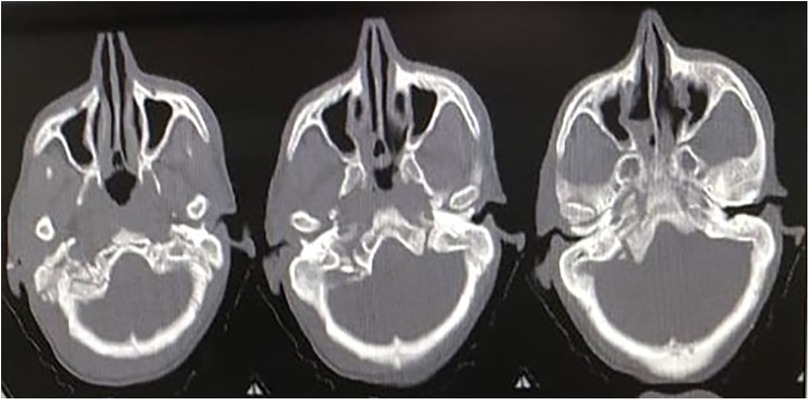

Another patient, a 45-year-old man, following an RTA, presented to the hospital with GCS E4V5M6, without any other injury. The following day, the patient began to notice hoarseness of voice, difficulty swallowing, and limited movement in the right shoulder. An NCCT brain scan was done, which was suggestive of a fracture of the right mastoid bone with extension to the occipital bone and a comminuted, undisplaced fracture of the right occipital condyle with a small chip in the jugular foramen (Figure 3). He was managed conservatively and fitted with a hard cervical collar for 3 months. His swallowing difficulty was mild due to which nasogastric tube feeding was not required. He showed improvement in his symptoms and remained symptom-free after 3 months.

Three axial CT scan slices of a human skull showing the nasal cavity and sinus regions. The images display the bone structures and soft tissues, with variations in density highlighted by different shades of gray.

Figure 3. NCCT of the second patient showing a comminuted, undisplaced fracture of the right occipital condyle with a small chip in the jugular foramen.